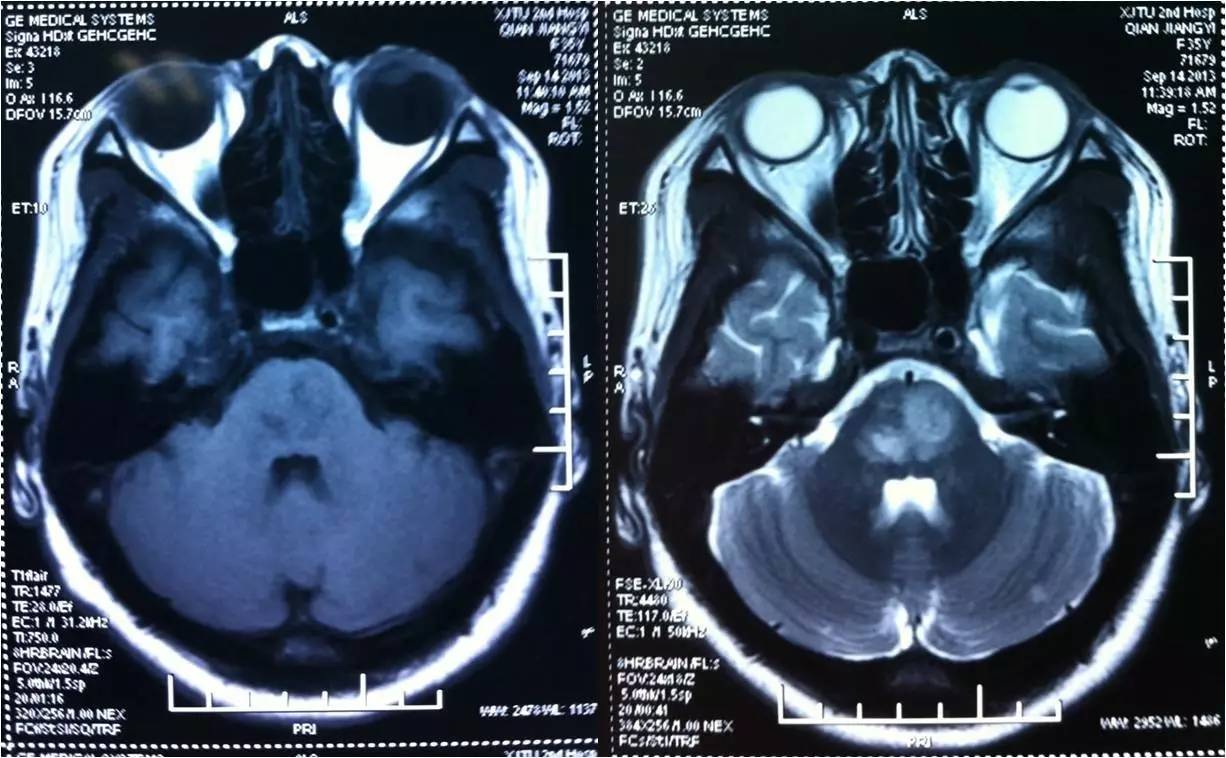

术前

3

术后

》意识清楚,言语流利,四肢活动自如;

》四肢肌力Ⅴ级;

》术后24小时NIHSS评分:0分;